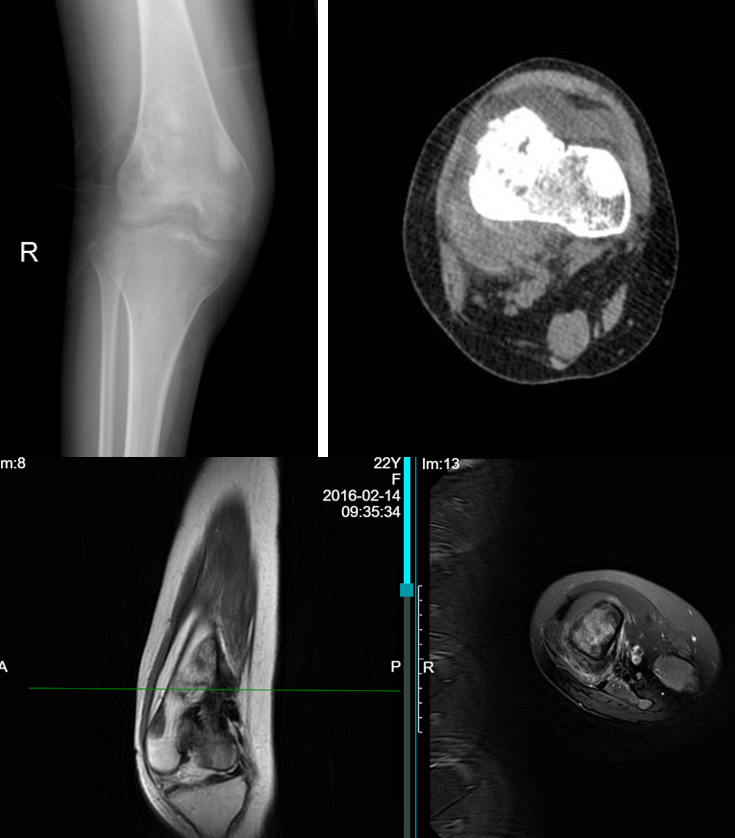

患者男性,36岁,7年前因左侧大腿疼痛就诊于外院,诊断为左股骨远端良性病变(骨纤维结构不良),7年内2次行肿瘤刮除+自体髂骨植骨术,术区骨质吸收,愈合不良。近1月来患者无诱因下左膝关节疼痛,活动后加剧,VAS评分4分,局部皮肤无发红,皮温正常